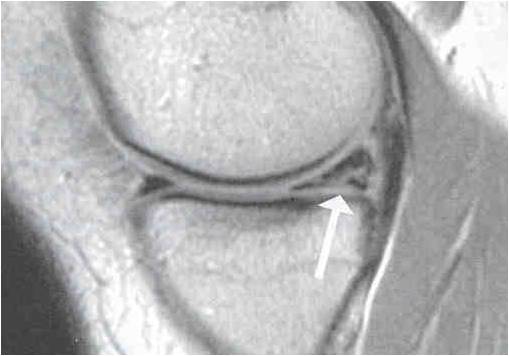

Diagnosis can be made via clinical examination of the knee. It is confirmed by MRI scan of the knee.

If at all possible, the torn meniscus should be repaired.

Inside-out repair of the torn meniscus.